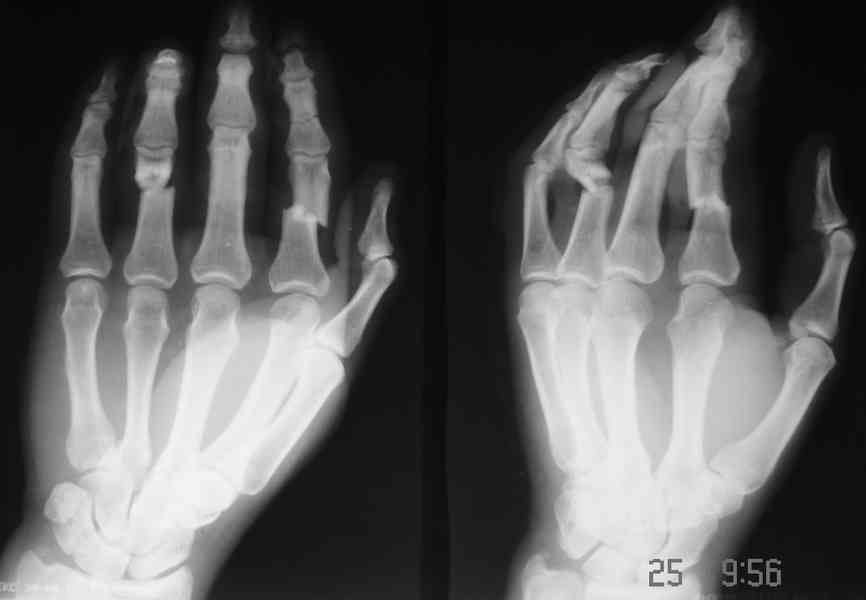

Комбинированная контрактура кисти

Уважаемые коллеги! Обратился больной с контрактурой 2-4 пальцев кисти. Травма год назад - рука попала в шнек. Планируется оперативное лечение.

Имеет-ли кто опыт укорачивающих остеотомий фаланг пальцев в подобных случаях?